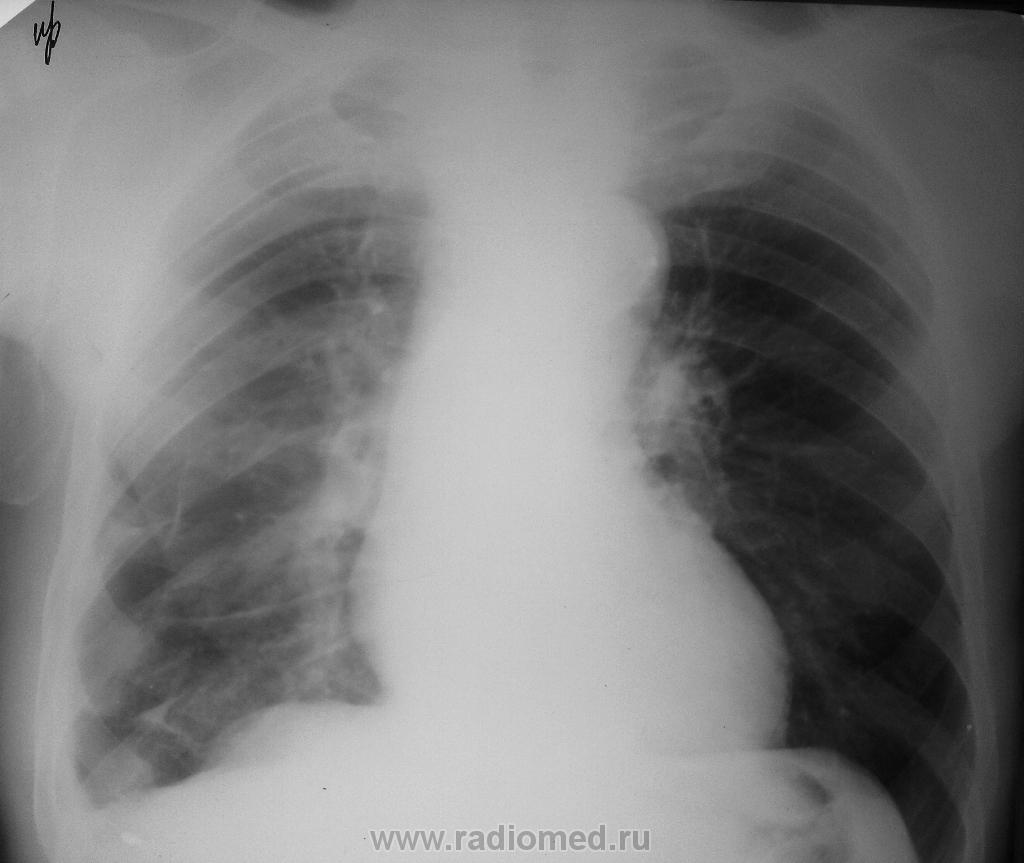

Легкие за 2 дня до скопии желудка:

На скопии прицельно со скошенной трубкой:

Случай трудный, Людмила Григорьевна, на свежую голову снова посмотрю. Сейчас скажу: на прицельных рентгенограммах не хватает контрастности в обл. анастомоза. Надо бы в таких случаях опорожнять пищевод в самом начале исследования.

Анастамоз явно нехороший (для анастомазита протяженностьбольшая) и тенюшка справа в легком. Если прошло 6 мес. после операции - рецидив, менее 6мес.- продолженный рост. Так -что продолженный рост, но все равно надо делать ФЭС для гистологического подтверждения

Может, у кого есть опыт в таких делах, подскажите по поводу протокола для пищевода... Я написала высокий риск рецидива, сложная киста (4 по Босняк) левой почки с озлокачествлением, мтс печени и единичный мтс правого легкого. Какие будут мнения и замечания?